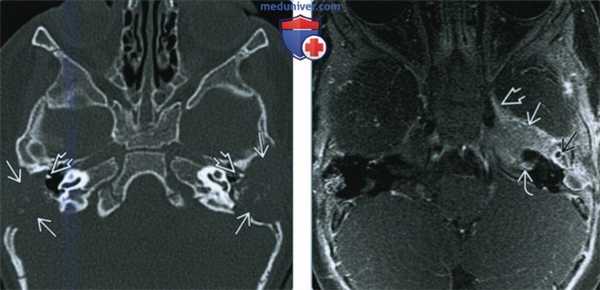

(Слева) При КТ в аксиальной проекции определяется объемное образование верхушки пирамиды левой височной кости, вызывающее фестончатость ушной капсулы (ЛКГ). Передний край объемного образования прилежит к каменистому сегменту внутренней сонной артерии.

(Справа) При МРТ Т1 с КУ в аксиальной проекции у этого же пациента с ЛКГ наблюдается однородное контрастирование объемного образования верхушки пирамиды височной кости. Видно, что к объемному образованию прилегает каменистый сегмент внутренней сонной артерии.